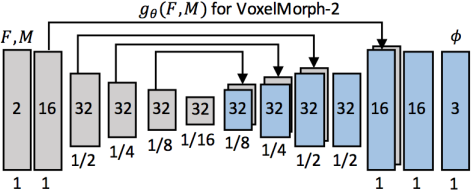

图2.1 voxelmorph encoder-decoder model结果,每个矩形表示3D volume,里面的数组表示channels,下面的数组表示空间分辨率。